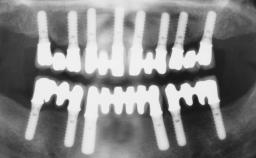

Immediate Loading of Four Implants in the Mandible and Final Restoration with a Full-Arch Metal Framework FDP

Pedro Tortamano, Luiz Otávio Alves Camargo

A fully edentulous 65-year-old woman was referred to our clinic for esthetic and functional dental rehabilitation. The patient presented with inadequate complete maxillary and mandibular prostheses, insufficient vertical dimension, and extensive tooth wear. The clinical examination and anamnesis showed no local or systemic contraindications, no signs or symptoms of bruxism, and an absence of smoking habits. The treatment proposed was implant placement in the mandibular interforaminal area and immediate loading with a fixed definitive prosthesis. A removable mucosa-supported complete prosthesis was indicated for the upper jaw, since its bone structure offered satisfactory retention and the financial condition of the patient disfavored a full-mouth implant-supported rehabilitation.

# of Implants 4

Type of Implants One-Piece

Prosthesis Type FDP

Loading Protocol Immediate

Retention Screw-retained, with 4 or more splinted implants Screw-retained, with 4 or more splinted implants